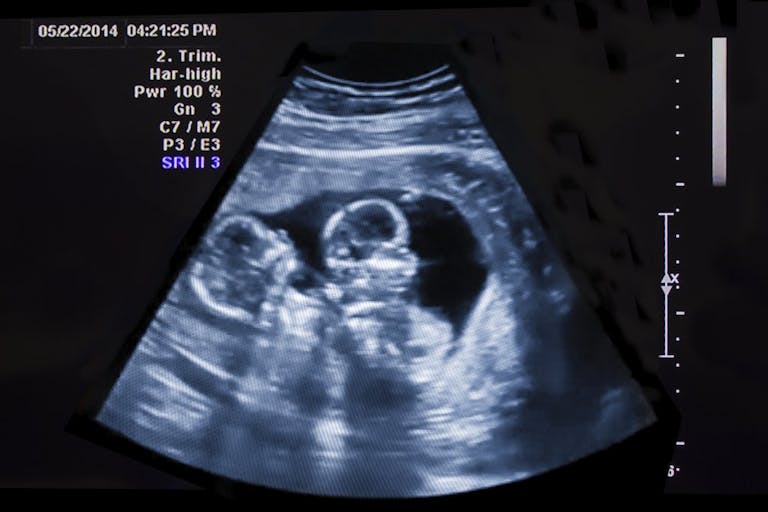

Superfetation is an extremely rare condition in which a woman gets pregnant, even though she is already pregnant. Virtually all known cases of superfetation involve assistive reproductive technology (ART), according to the Cleveland Clinic. In the Searles’ case, it meant carrying a pair of twins who were at two different gestational ages.

“Firstly, I was trying to wrap my head around being pregnant with two babies with two different gestations,” she said. “So I was continuously having to explain to medical experts that I was expecting two babies … with one baby at six weeks and one baby at eight and a half weeks. And nobody could understand why. So it was just complicated from day [one]. And I was so sick, and it lasted all the way up until having the babies.”